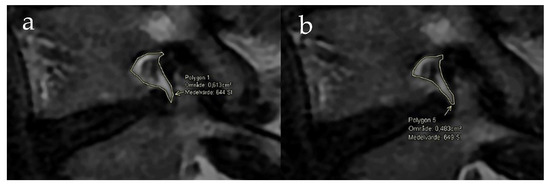

2.3. Evaluation of MRI Investigations

3.2. Foraminal Area Measurements